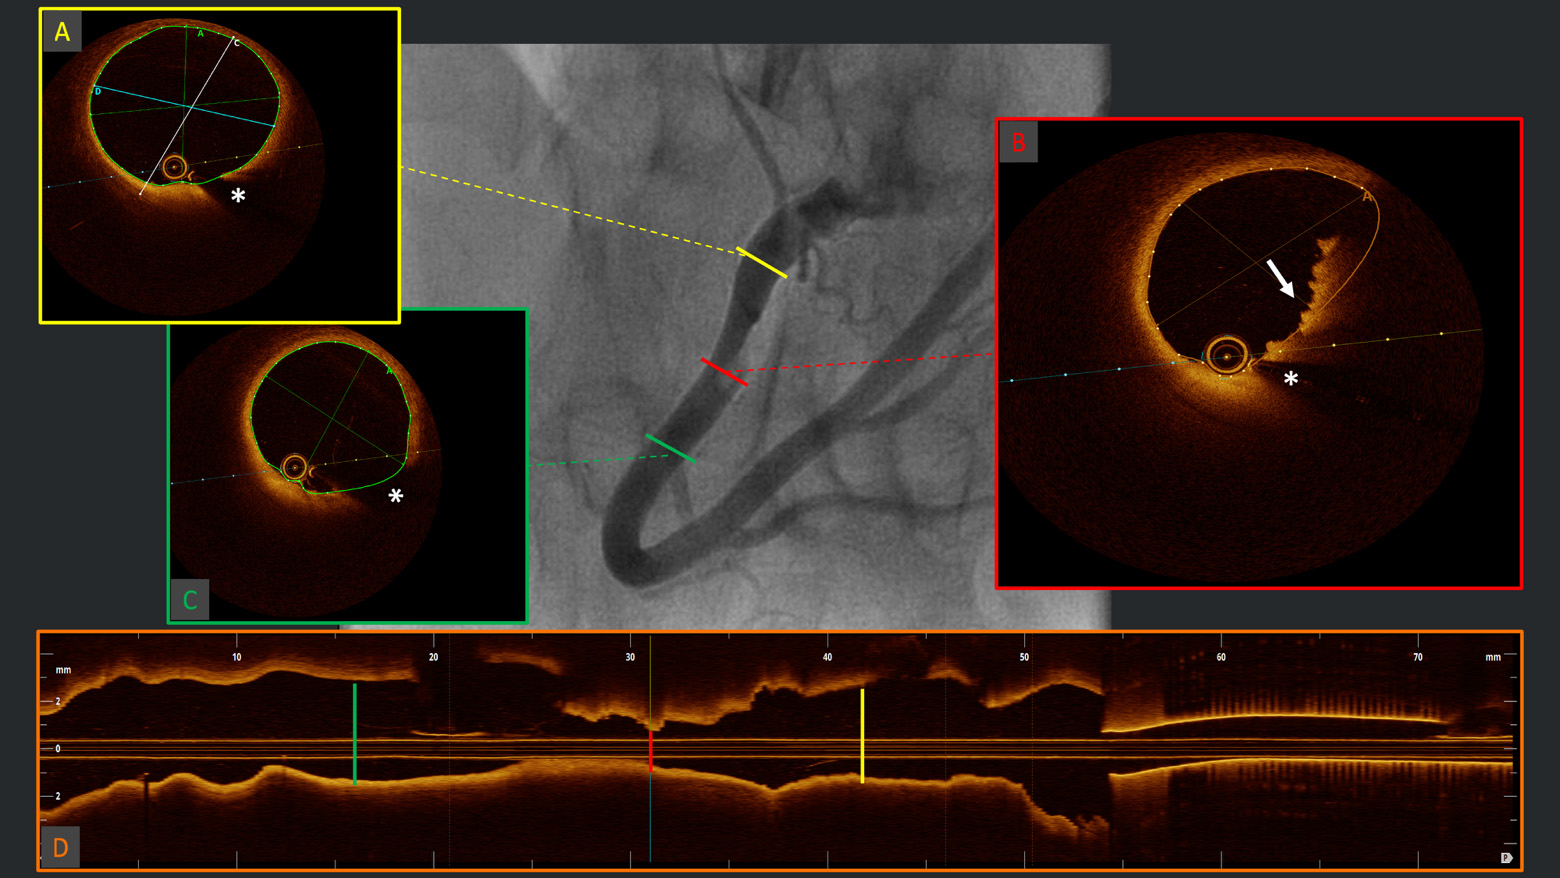

Compared to IVUS, OCT can more precisely characterize calcium morphology, defining not only the arc, length and depth of calcium distribution—fundamental predictors of stent under-expansion [24]—but also allowing critical distinction between eruptive and non-eruptive calcified nodules [59]: the former represents a relatively rare cause of acute coronary syndrome (2–7%) and is characterized by good deformability and good acute result but a high rate of recurrence (in-stent re-protrusion); the latter is characterized by a higher degree of calcification at vessel level, which often requires multimodality plaque modifying technologies (i.e., RotaTripsy, RotaCut, etc., [60, 61]) to achieve good acute results, although show lower rates of TLR at follow-up. Examples of different calcium morphologies at OCT analysis, are shown in Fig. 3.

Fig. 3. Calcium burden assessment and characterization. Example of two different calcium morphologies at OCT analysis: (A) eruptive calcified nodule in the context of acute coronary syndrome with disrupted fibrous cap (white arrow), overlying red thrombus with high attenuation (dashed arc) and evidence of high calcium burden (green arrow); (B) severe 360° calcification (dashed circle) with thick calcium (two-headed arrow) but intact fibrous cap (white arrow) indicating a probable stable lesion. *Wire artifact.